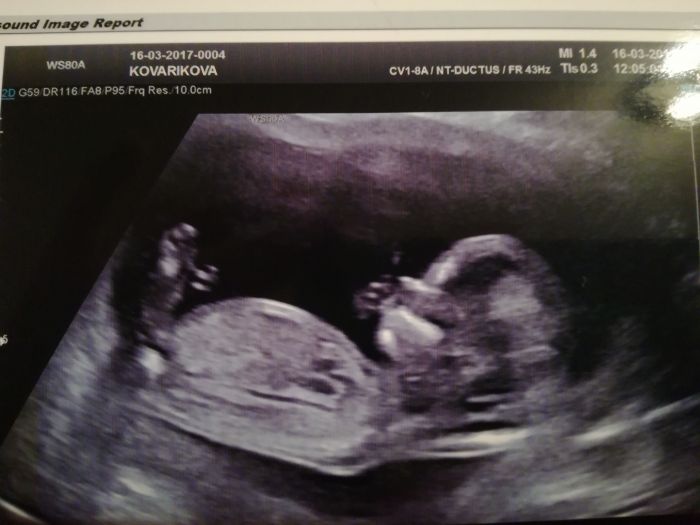

Tak ja mam screening uz take za sebou. Marci158,take mam termin 18.9. Na fotce ma mimi skoro stejne brisko jako to nase?. Mimco se pri kontrole taky mrskalo,dokonce stalo i na hlave?. Pry je vse ok a zatim to vypada na holcicku. Doma uz jednu 2r mame. Hezky den.

Tak ja mam screening uz take za sebou. Marci158,take mam termin 18.9. Na fotce ma mimi skoro stejne brisko jako to nase?. Mimco se pri kontrole taky mrskalo,dokonce stalo i na hlave?. Pry je vse ok a zatim to vypada na holcicku. Dima uz jednu 2r mame. Hezky den.

Tak ja mam screening uz take za sebou. Marci158,take mam termin 18.9. Na fotce ma mimi skoro stejne brisko jako to nase?. Mimco se pri kontrole taky mrskalo,dokonce stalo i na hlave?. Pry je vse ok a zatim to vypada na holcicku. Doma uz jednu 2r mame. Holky taky jste tak unavene? Ja se v noci tech 9 hod v klidu vyspim,s malou vstavame v 8,ale kol poledne uz ssm uplne ko?Hezky den.